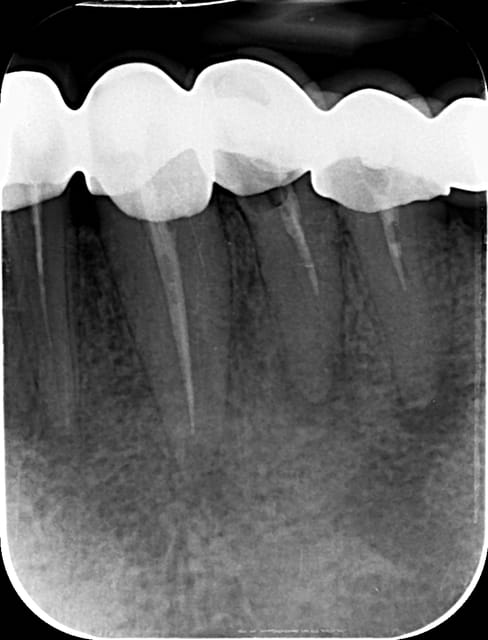

Bonjour a tout !

Initial e après obturation

joli travail.

Obturation gutta à chaud j'imagine?

no !!! condensation latérale à froid est alors verticale chaud... e buildup